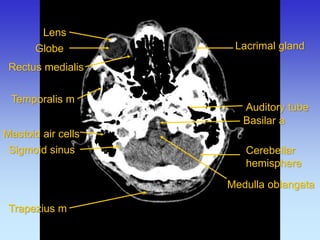

Lens

Globe

Auditory tube

Lacrimal gland

Mastoid air cells

Medulla oblangata

Rectus medialis

Temporalis m

Cerebellar hemisphere

Trapezius m

Sigmoid sinus

Basilar a